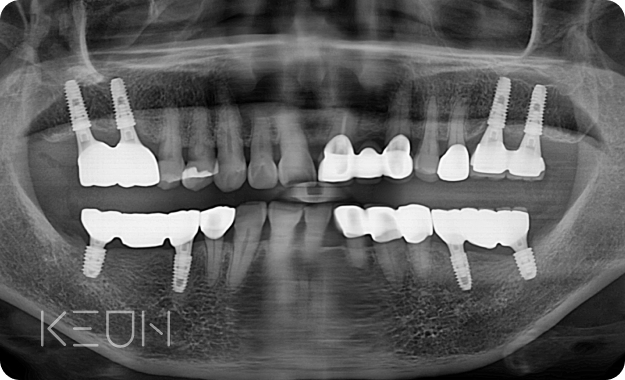

어르신 복합치료 전후사진.

- After

- Before